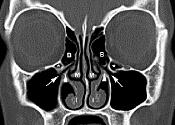

Napkin Notes: Sinuses & CT Scan

I feel like a character in a scifi horror movie.  Namely, the one who comes back from a routine jaunt on the surface of an alien planet feeling fine and dandy, only to realize hours later that she has been somehow mysteriously mutated by alien DNA or impregnated with a terrifying little pod baby. After two courses of antibiotics for a sinus infection, I am still having pressure headaches in my face and head most of the day (worse at night). … At any rate, we’re at the part of the movie where the audience finally finds out what’s going on.  At least I hope we are.  Dr. B scheduled me for a CT scan of my sinuses today/ Katrina , Notes on a Napkin. More here .